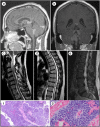

Ewing sarcoma (ES) is an aggressive, high-grade neuroectodermal neoplasm that frequently manifests in children and young adults. Although ES without osseous involvement most commonly involves paravertebral regions of the spine, it very rarely presents as a primary intracranial tumor. This report discusses a unique presentation of an adult extraosseous ES arising from the pineal region with extension into the third and fourth ventricles and multiple drop metastases to the spine. This case demonstrates the application of current chemotherapeutic and adjuvant management and offers insight into possible treatment modalities for metastasis in an atypical extraosseous ES involving the brain and spine.